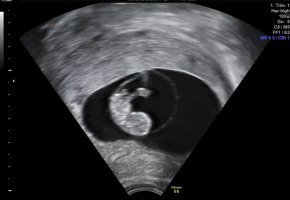

Første tidlige ultralyd 8+5

Her er bamsemumset vårt, med bankende hjerte

For en følelse! For en glede! Lille venn har navlesnoren i morkaken nå så den mest kritiske fasen var over sa jordmor. Alt så helt supert ut

Hun målte lille til 2,13 cm og nøyaktig 8+5 i dag, som er nøyaktig samme dagen jeg har